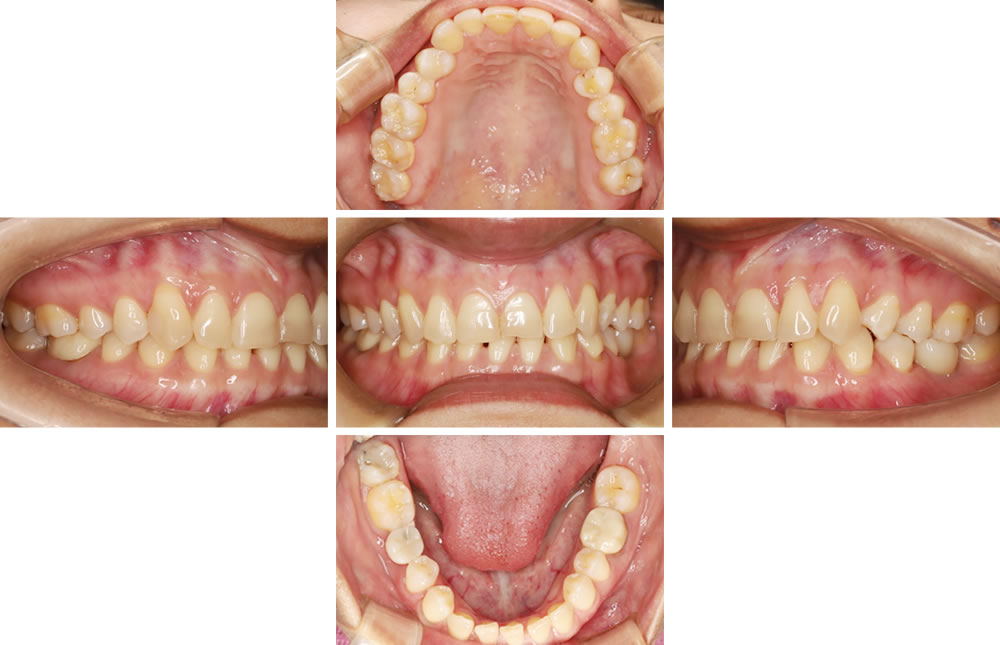

③他院で抜歯した部分をインプラントで治療した症例

こちらの患者さまは他院でむし歯だったところを抜歯し、インプラント治療ができないと診断されたので当院で診てほしいという主訴で来院されました。患者さまと相談し、入れ歯にはしたくないとのことでしたので、インプラントで噛み合わせを回復する計画を立てました。

パノラマレントゲンにて診断後、インプラント埋入用のステント(インプラントの方向性や埋入深度を決めるためのマウスピース)を作成しました。その後、ステントを口腔内に入れてCTを撮影し、十分な骨の厚みを確認した後に埋入方向を決定しました。

インプラント手術の実施

ステントを使用して計画通りの位置にインプラントを埋入しました。その後、2ヵ月の治癒期間を経て、当該歯の最終的な上部構造(被せ物)の型取り・作成を行いセメントにて仮固定しました。(当院はもしもの状況に備えるため、基本的に仮固定しておりますが普段の生活で脱離してしまうことはほとんどございません。)

インプラント治療前後の比較

審美的・機能的共に改善し、患者さまにも大変ご満足いただけました。現在は3ヵ月のメンテナンスで良好な経過を追っています。

| 年齢・性別 | 30代女性 |

|---|---|

| 治療期間 | 3ヵ月/6回 |

| 治療費(税込) | 440,000円 (※治療費等の変更により現在の費用と異なる場合があります) |

| リスク・注意点 | ・メンテナンスの仕方次第でインプラント周囲炎になる可能性があります。 ・咬合力によってインプラント体が破折する可能性があります。・骨量によっては骨を作る処置が必要になったり、治療自体ができない場合があります。 ・糖尿病など、全身状態によっては治療が受けられない場合があります。 |